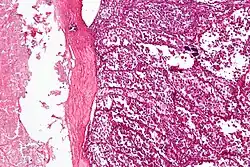

Makroskopowo guz jest słabo odgraniczony, o miękkiej, kruchej konsystencji. Na przekroju jest koloru szarego do żółtawego[5]. Często, szczególnie w dużych zmianach, są obecne duże ogniska martwicy i krwotoków[5][12]. Guz może być otoczony licznymi krętymi naczyniami[5].

W obrazie mikroskopowym charakterystyczna jest obecność gęstego beleczkowania o zróżnicowanej grubości dzielącego utkanie guza na gniazda komórek nowotworowych. W przegrodach łącznotkankowych obecne są cienkościenne naczynia krwionośne wyłożone pojedynczą warstwą spłaszczonych komórek nabłonkowych[5]. W obrębie centrum gniazd komórek widoczna jest martwica i utrata spójności komórek (kohezja), co jest przyczyną utworzenia charakterystycznego pseudopęcherzykowego wzoru utkania[5]. Rzadziej utkanie jest bardziej lite, szczególnie u niemowląt i u dzieci, komórki są ułożone w rozproszone arkusze bez tworzenia układu gniazd i pseudopęcherzyków[12][13].

Komórki nowotworowe są duże, okrągłe lub wielokątne, wyraźnie ograniczone, wykazują pewną niewielką zmienność wielkości i kształtu. Komórki zawierają obfitą ilość eozynofilnej, rzadziej jasnej, drobnoziarnistej cytoplazmy, jedno lub dwa pęcherzykowate jądra komórkowe z jednym jąderkiem[5][12]. Atypia jądrowa jest rzadka[12]. Aktywność mitotyczna jest niewielka i liczba figur mitotycznych jest uboga[5]. Niemal stałą cechą jest inwazja naczyń krwionośnych[12][14]. Barwienie PAS ujawnia wewnątrzkomórkowy glikogen oraz kryształy w kształcie pręcików zbudowane z białka transportującego kwasy monokarboksylowe (MCT1) i CD147[5][15]. Kryształy mają znaczenie diagnostyczne, występują one w około 80% przypadków mięsaka pęcherzykowego[13].

Materiał pobrany podczas biopsji lub preparat pooperacyjny jest barwiony i oceniany pod mikroskopem. Obraz mikroskopowy mięsaka pęcherzykowego po wybarwieniu H+E jest charakterystyczny. Typową jest obecność pseudopęcherzyków, gniazd komórkowych i łącznotkankowych przegród z cienkościennymi naczyniami[7][13]. Nowotwór różnicuje się przede wszystkim z pęcherzykowym mięśniakomięsakiem prążkowanokomórkowym, przyzwojakiem i przerzutami raka nerki[8].